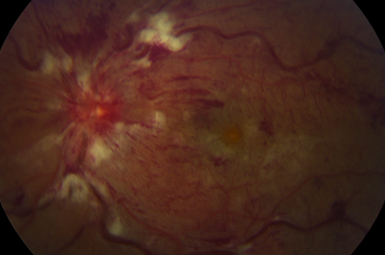

Retinal Vascular Occlusion

Arteriosclerosis can lead to retinal blood flow problems and impaired vision. Injections, laser, and/or surgery frequently improve vision.